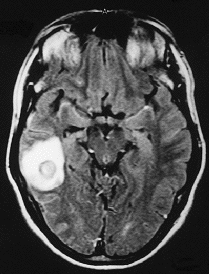

Varón de 43 años, con antecedentes de síndrome de Rendú-Osler (SRO), que ingresó en el servicio de cuidados intensivos tras haber sido sometido a neurocirugía por ser portador de un absceso cerebral único. El paciente manifestó haber comenzado hace un mes con episodios de hipertermia y convulsiones aisladas, por lo que se le practicó una resonancia magnética en la que se visualizaba una imagen en el área temporoparietal derecha (fig. 1). Debido al antecedente de SRO, la presencia de hipoxemia refractaria al suministro de oxígeno y la asociación del síndrome con fístulas arteriovenosas, se le practicó una angiorresonancia magnética pulmonar que mostró la presencia de una gran fístula arteriovenosa pulmonar (fig. 2) que corroboraba las manifestaciones clínicas desarrolladas por el paciente. Fue tratado con antibióticos y derivado al servicio de hemodinamia intervencionista para embolización de la fístula como tratamiento definitivo.

Fig. 1.